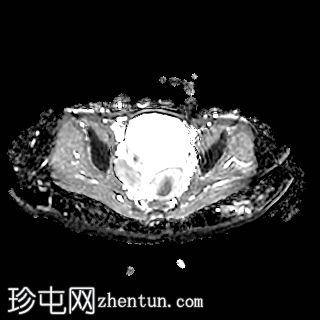

轴位

T2加权像

右侧卵巢增大,卵泡呈周边排列。

附件血管蒂扭转(漩涡征)。

右侧附件旁可见一较大的、边界清晰的盆腔囊性病变,向右倾斜,提示为卵巢旁囊肿。

本病例展示了卵巢扭转的典型影像学特征,包括卵巢增大、卵泡呈周边移位、卵巢向内侧偏移以及特征性的漩涡征。

在这种情况下,较大的卵巢旁囊肿被认为是发生卵巢扭转的高危因素。如果卵巢旁囊肿较大(>5厘米)或活动度较大,其重量/活动度增加会牵拉附件,导致卵巢和输卵管发生扭转。